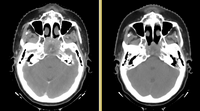

Anatomic change due to tumor regression in nasopharyngeal cancer

Head and neck cancers account for about 60,000 new cancer cases per year and represent about 6% of all cancers in the United States [1]. These cancers are treated by a combination of chemotherapy, radiotherapy, and surgery. The five-year survival is approximately 50%. During a six-week regimen of radiotherapy, head and neck cancer patients often exhibit anatomic changes that affect their treatment. These changes include tumor regression or growth, changes in lymph node size, and changes in air cavities. Uncorrected, these changes can increase the risk of treatment complications or reduce treatment efficacy.

Adaptive radiotherapy addresses the problem of anatomic change by incrementally adjusting the radiotherapy plan, and is a prime example of personalized medicine. A mid-treatment adjustment is complex: it requires a new CT image, image segmentation, deformable registration, and mapping of the previously delivered dose onto the new image. This project proposes to use the NA-MIC Kit to develop a simple, practical workflow for achieving adaptive radiotherapy which can be applied on a case-by-case basis.